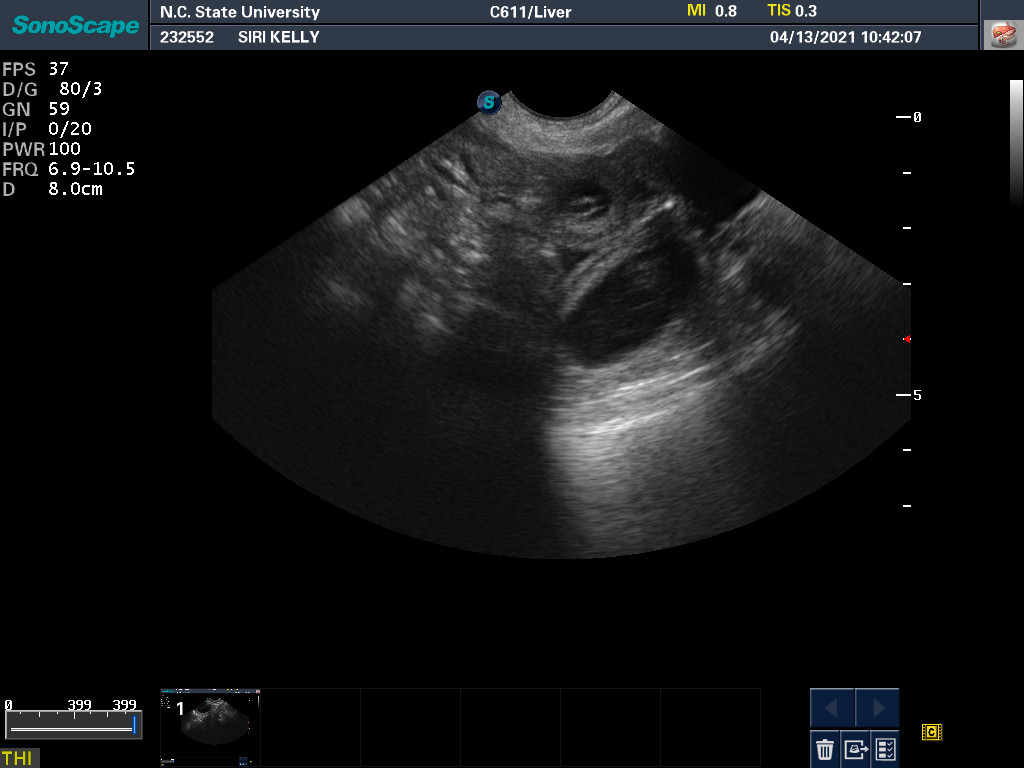

13 Apr

Ultrasound today by the theriogenology (reproduction) veterinarians at NC State University showed that Siri is pregnant with possibly four puppies. (It can be difficult to accurately count puppies using ultrasound.)

If all goes well, puppies are due around 18 May.